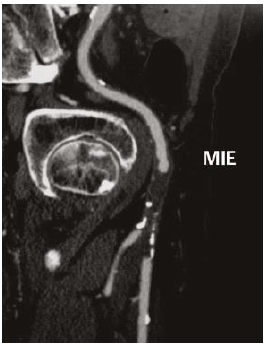

José Carlos, 64 anos, queixa-se de lesão dolorosa pós-traumática em extremidade do hálux esquerdo há 14 dias. Hipertenso, dislipidêmico e tabagista. Ao exame, ambos os membros inferiores apresentam pulso femoral 3/3+ e pulso poplíteo e distais ausentes. Hálux direito apresenta gangrena seca de sua extremidade. Comparece com o seguinte exame complementar solicitado pelo médico anterior: